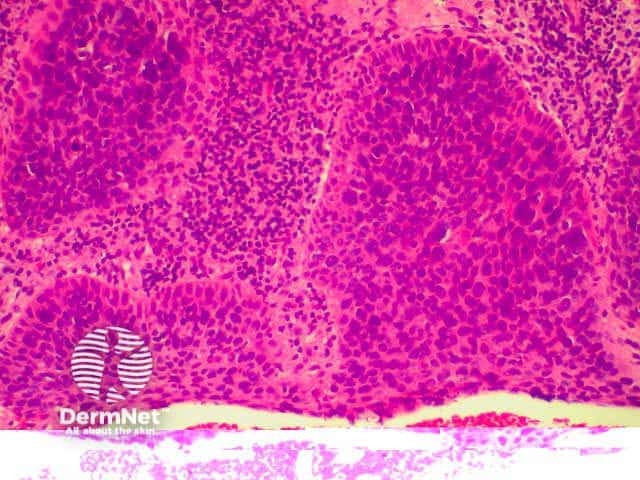

Benign and malignant tumours of inflammatory cells may involve the skin primarily or secondarily. The majority of these are lymphomas, which may be of T or B cell type. These tumours are uncommon, and only Mycosis Fungoides (a form of cutaneous T cell lymphoma- CTCL) will be described. Cutaneous T-cell lymphoma (CTCL) arises from the skin. Link to a clinical description of cutaneous T-cell lymphoma.

Mycosis fungoides is the most common form of CTCL and has several stages including patches, plaques and tumours. In early patch stage disease, it may not be possible to make a histological diagnosis of MF, and repeat biopsies as the disease progresses may be required, even when the clinical suspicion is strong.

The histological features of mycosis fungoides include: